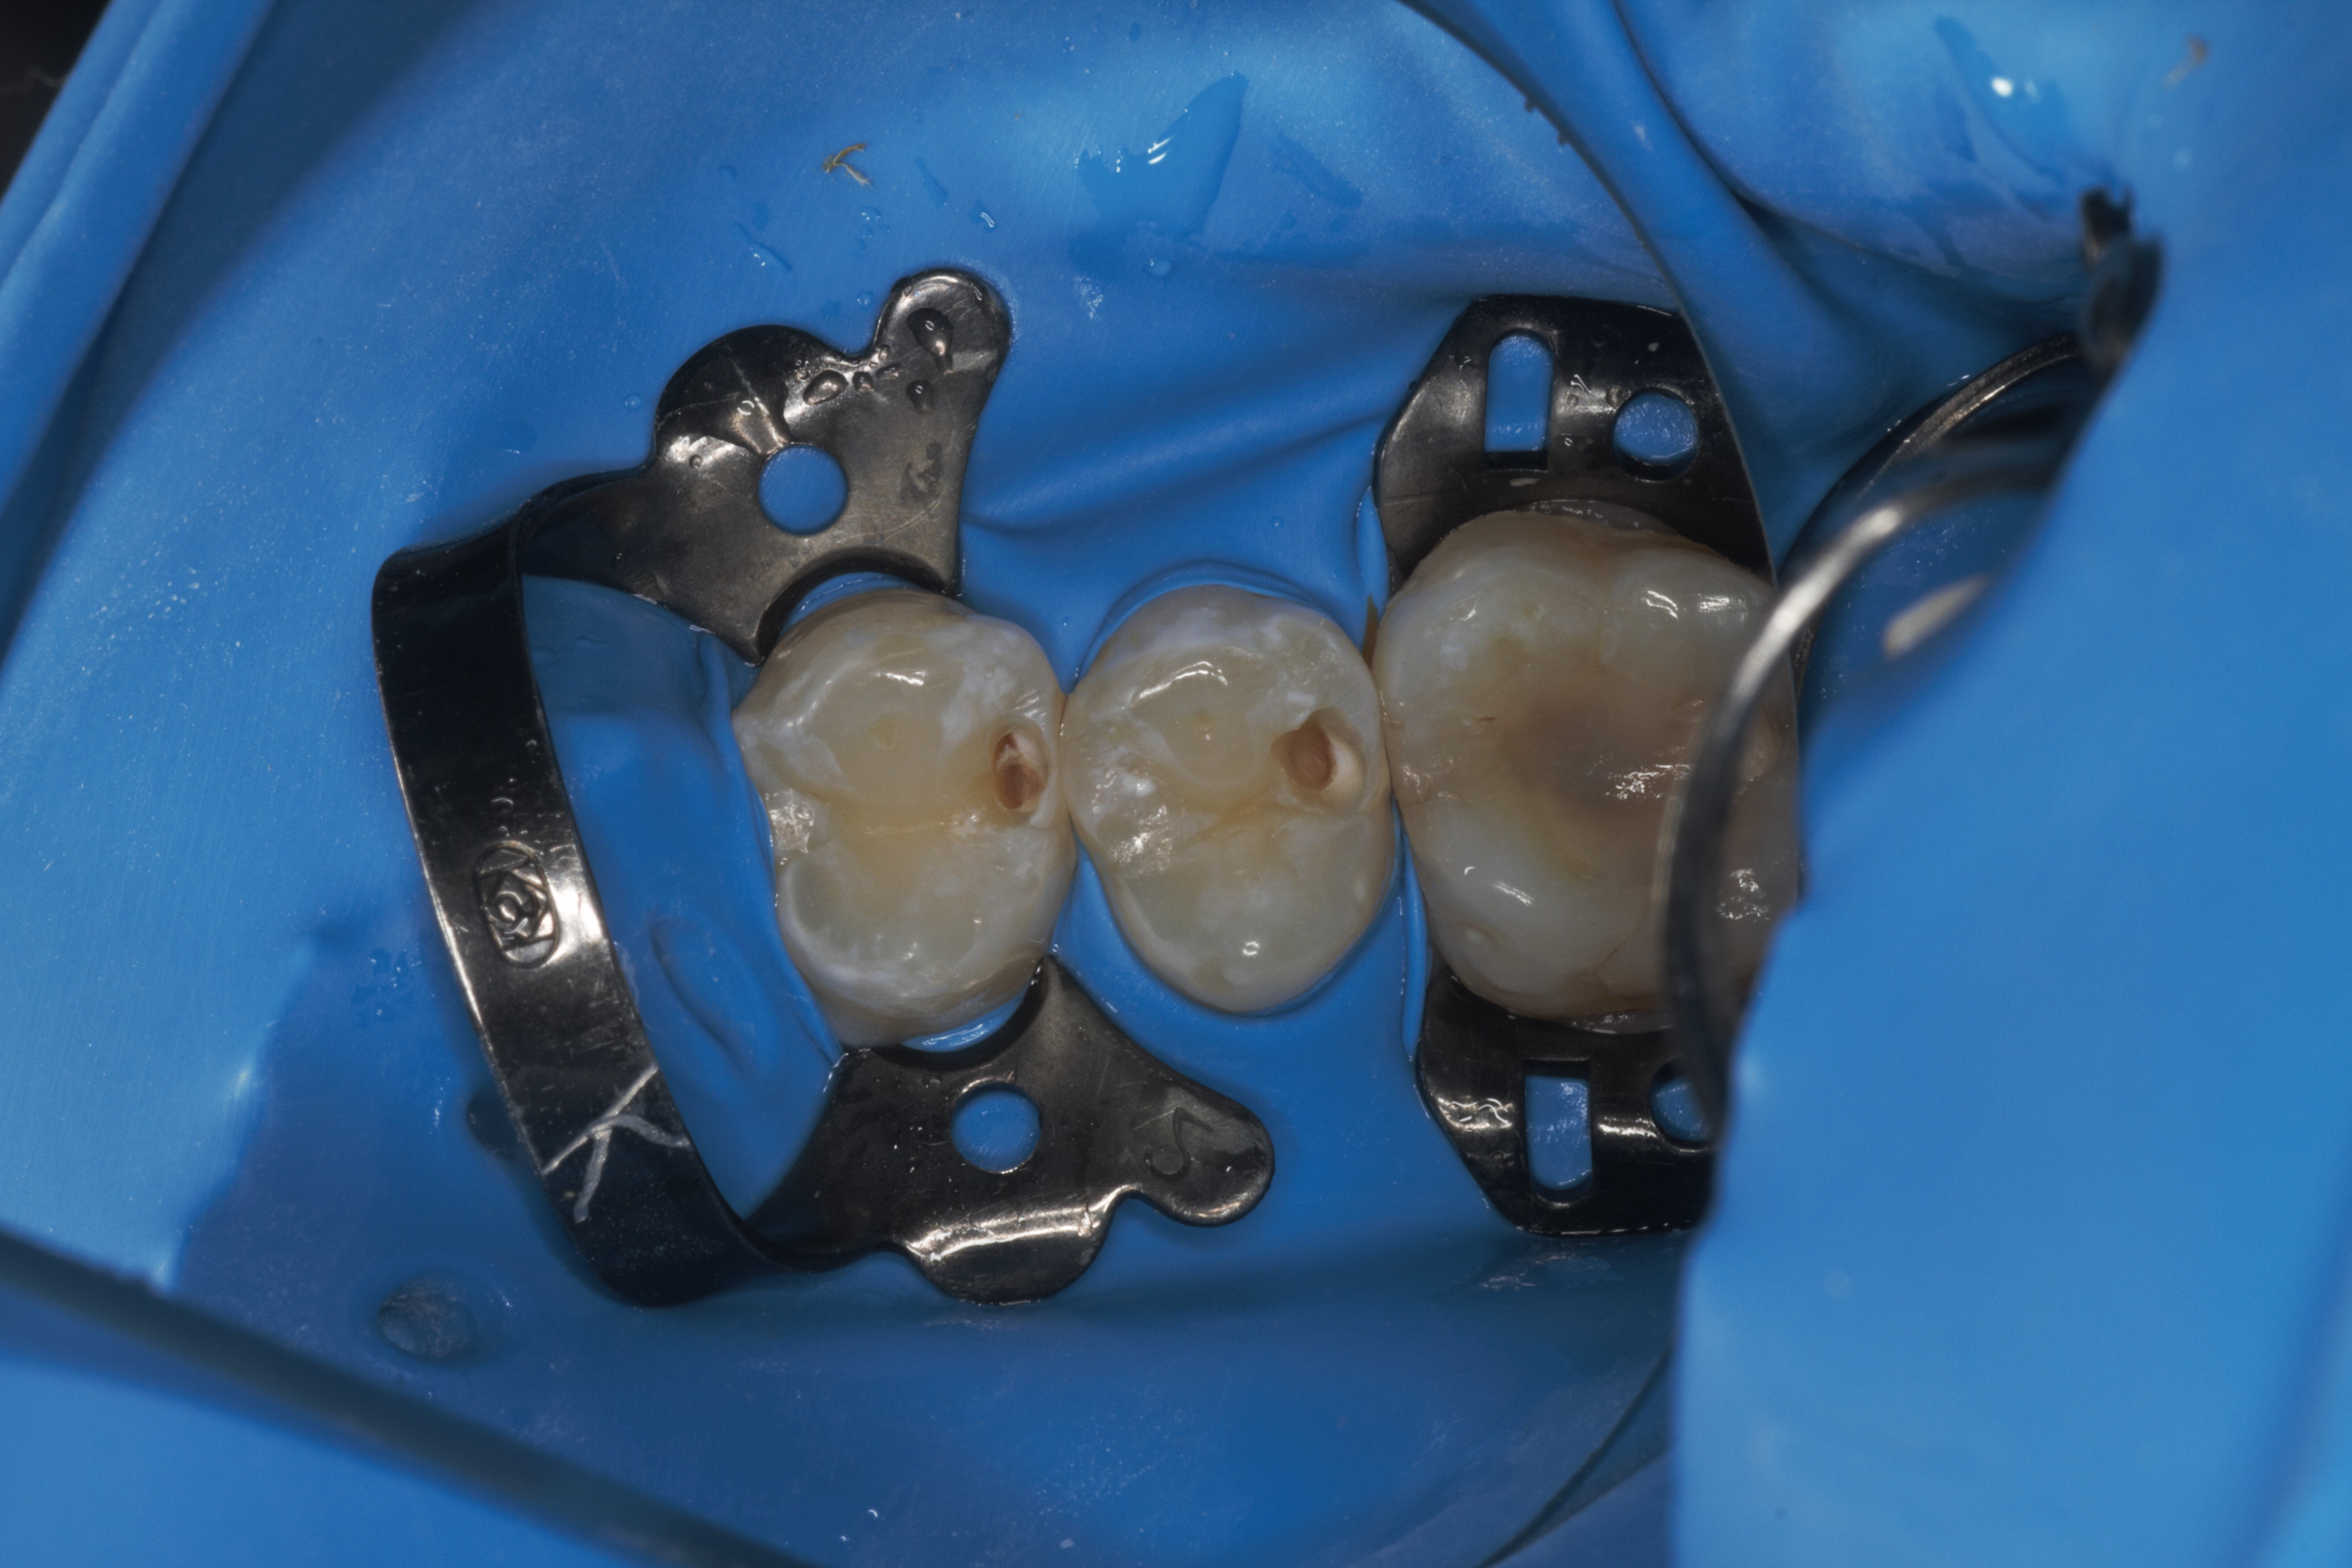

- Эстетическая реставрации жевательной и фронтальной группы зубов современными пломбировочными материалами, диагностика кариеса на ранних этапах развития, предупреждение образования вторичного кариеса в области запломбированных зубов